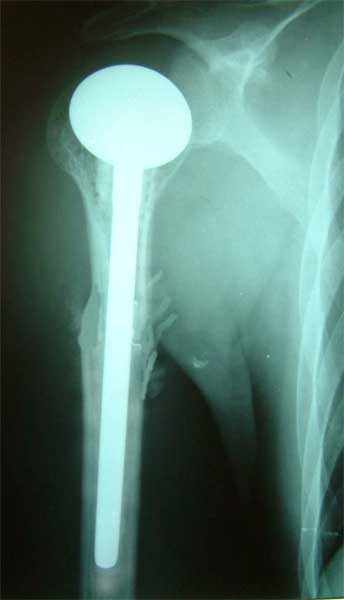

肱骨近端软骨肉瘤,肿瘤段截,用13厘米长的异体骨,

修复肱骨近段,人工肱骨头置换术后3年